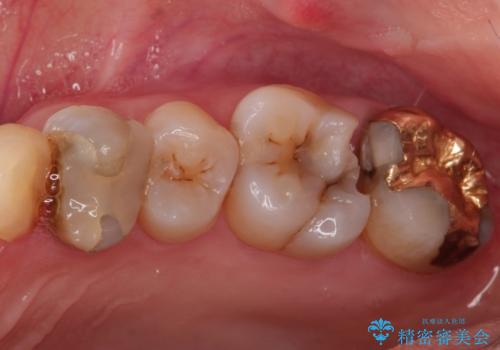

メタルインレーからセラミックインレーへ

- メタルインレーによる審美障害を主訴に来院されました。

セラミックインレーに治療を行っております。

e-max プレスインレーにて修復治療を行っているため適合性及び審美性の高い治療を行うことができます